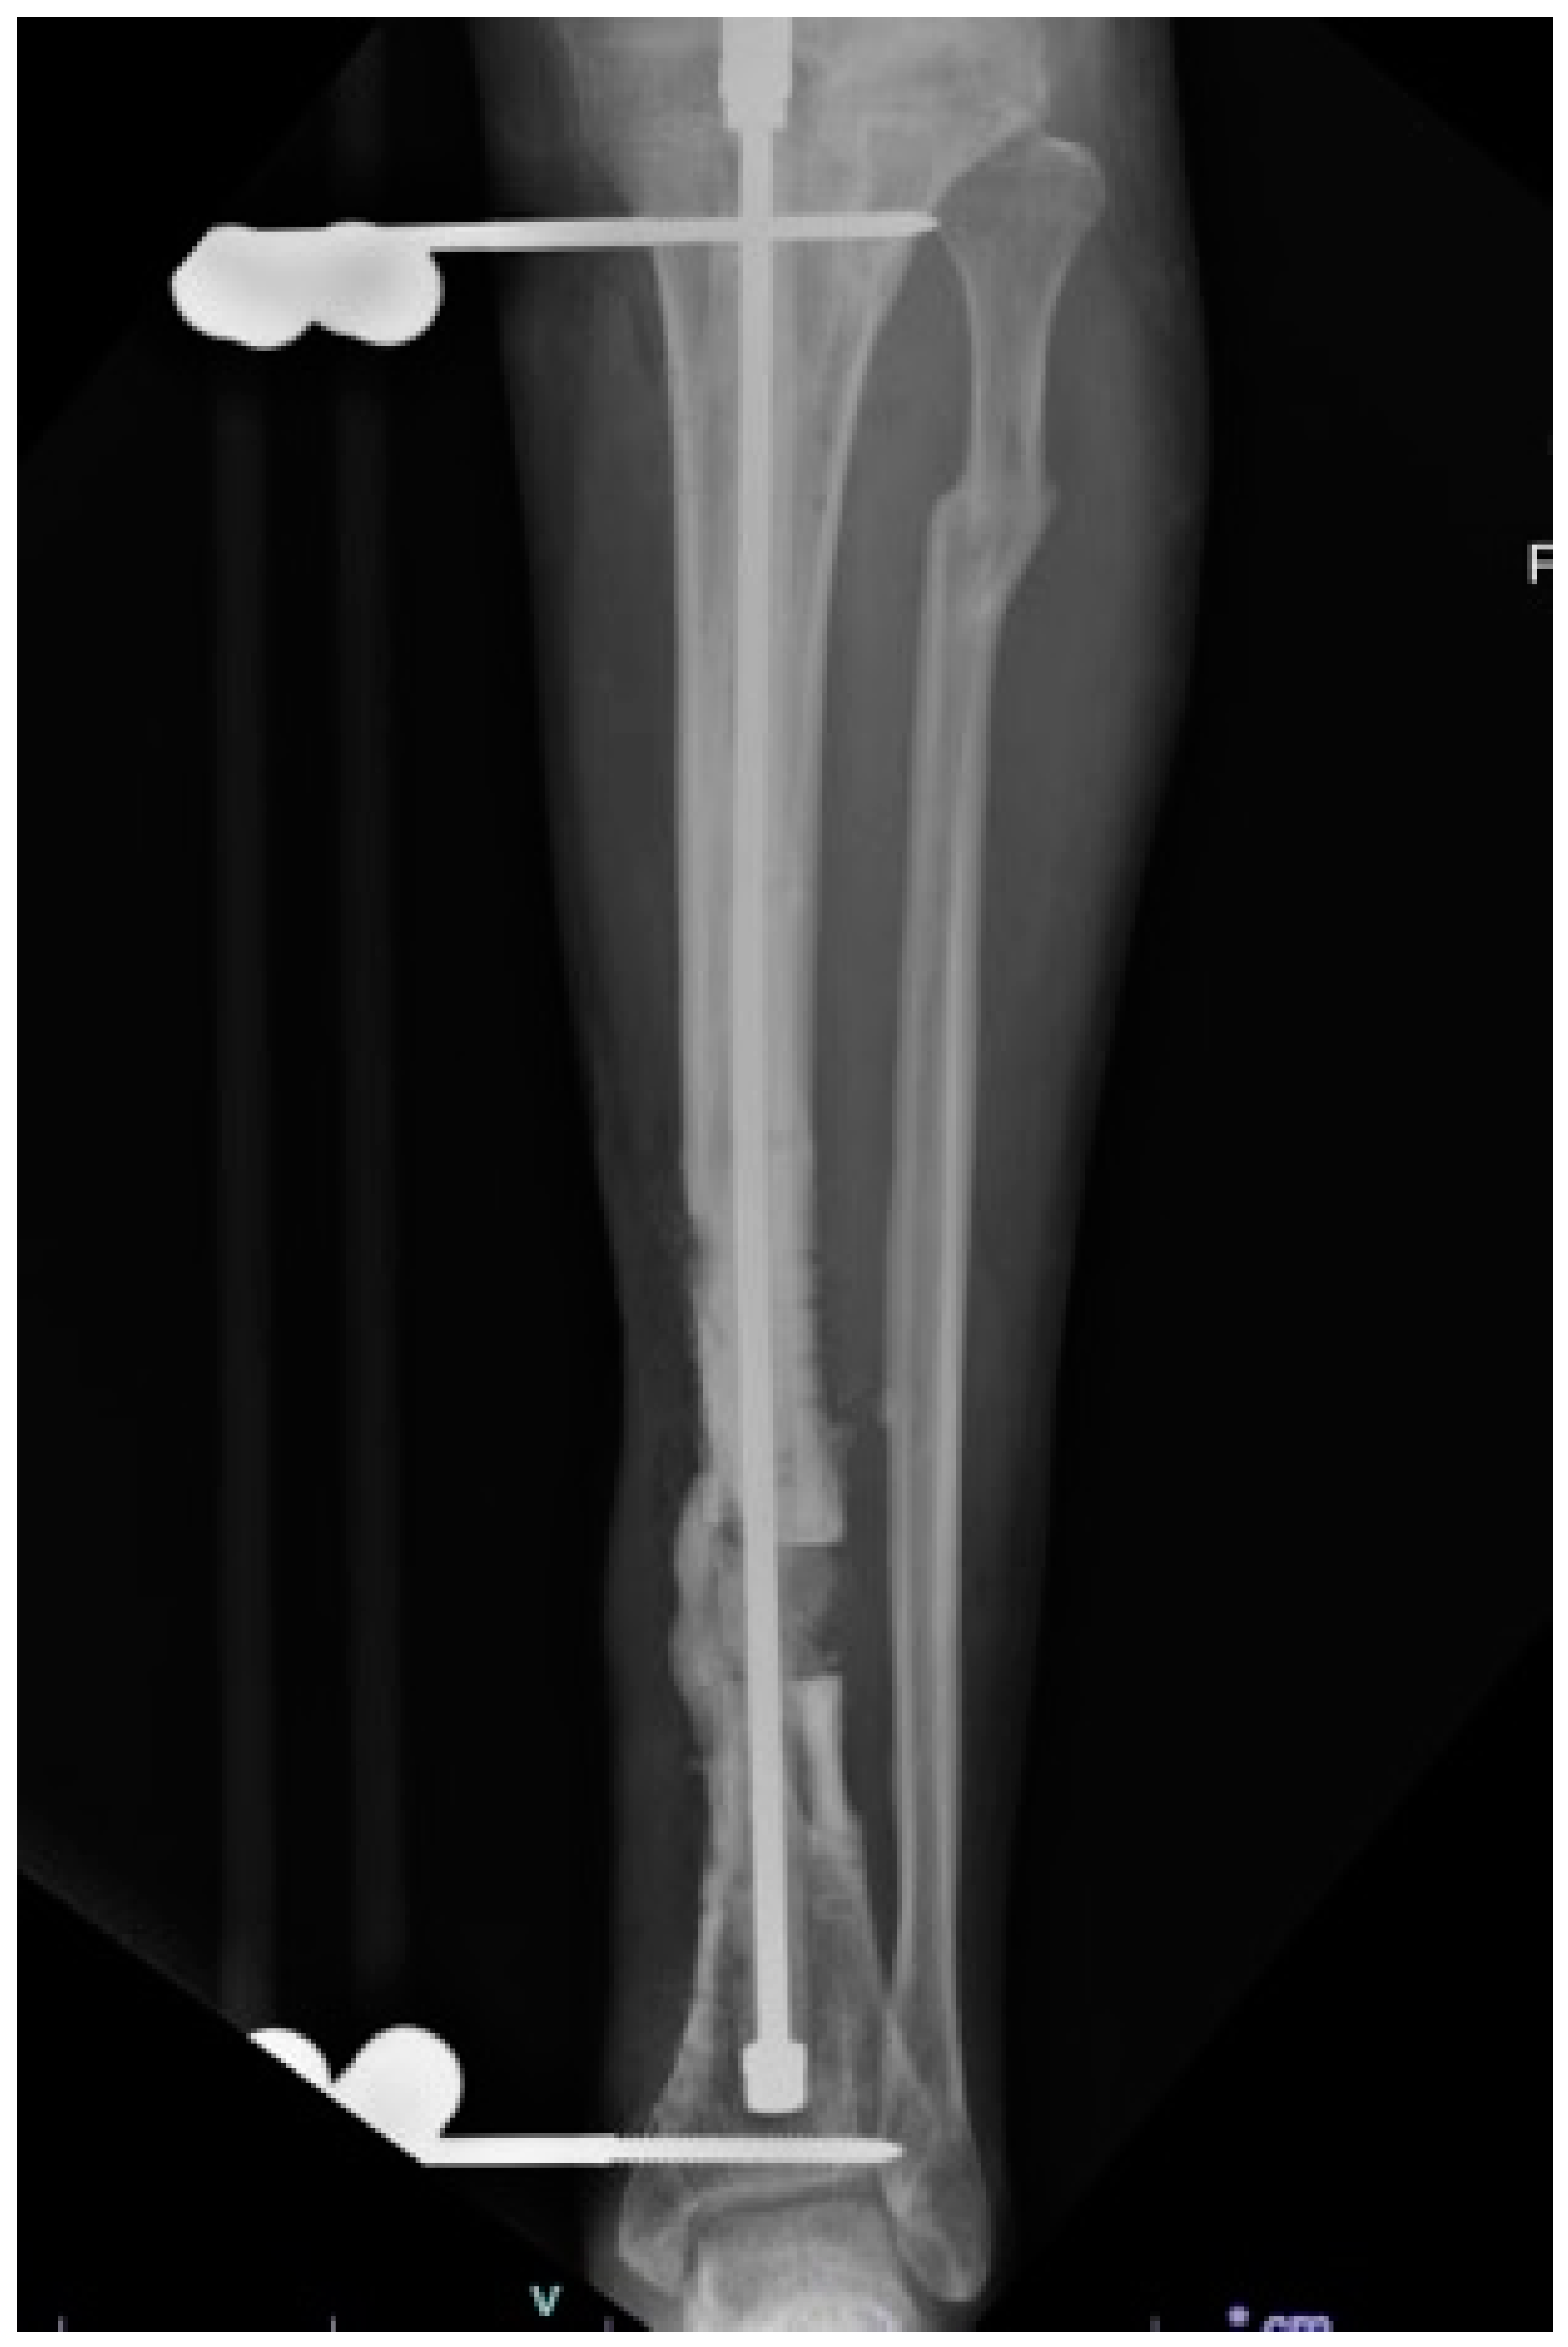

- Gulabi, D.; Erdem, M.; Cecen, G.S.; Avci, C.C.; Saglam, N.; Saglam, F. Ilizarov Fixator Combined With an Intramedullary Nail for Tibial Nonunions With Bone Loss: Is It Effective? Clin. Orthop. Relat. Res. 2014, 472, 3892–3901. [Google Scholar] [CrossRef]